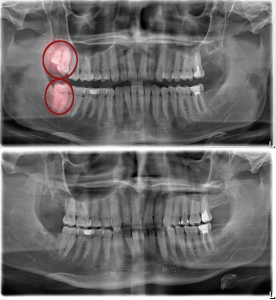

Before & After

Sumber: https://www.peaceperio.com/wp-content/uploads/2019/11/scaling-before-after.jpg